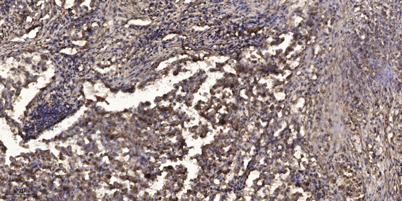

| Product name: | Rab 38 rabbit pAb |

| Dilutions: | WB 1:500-2000;IHC-p 1:50-300 |

| Immunogen: | The antiserum was produced against synthesized peptide derived from human RAB38. AA range:80-129 |